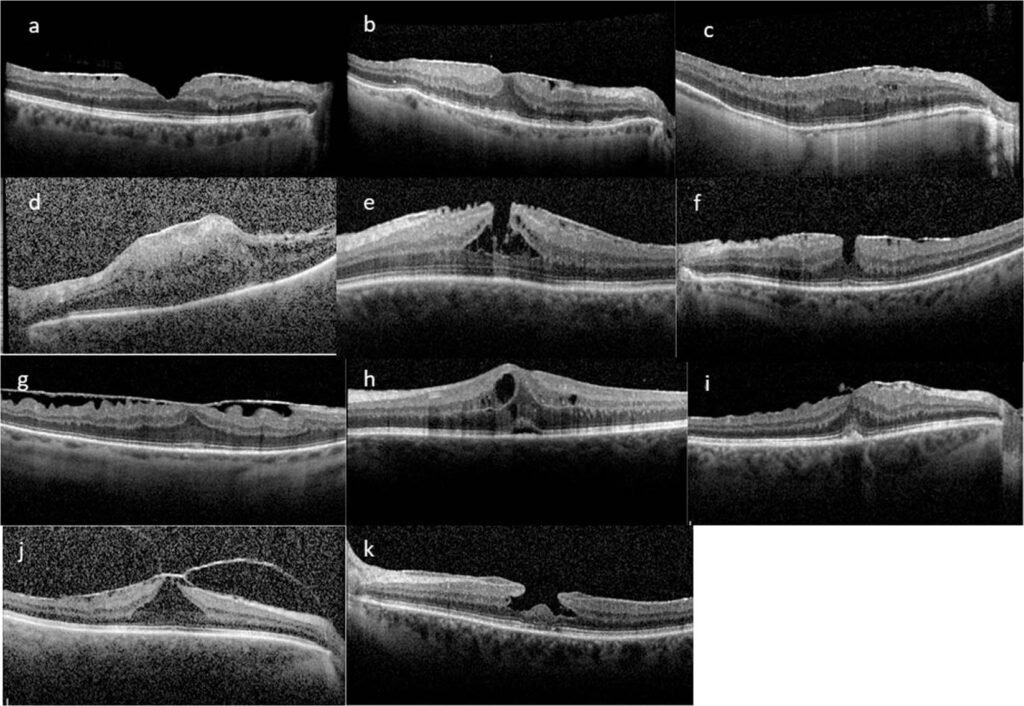

For at forstå helingsprocessen er det vigtigt først at forstå selve tilstanden. Dit øje er fyldt med en geléagtig substans kaldet glaslegemet. Med alderen kan dette glaslegeme skrumpe og trække sig væk fra nethinden – en proces kaldet posterior glaslegeme-løsning (PVD). Dette er en normal del af aldringsprocessen, men nogle gange kan det stimulere dannelsen af et tyndt lag arvæv på overfladen af makula. Makula er den lille, men ekstremt vigtige del af din nethinde, der er ansvarlig for dit skarpe, detaljerede centralsyn, som du bruger til at læse, genkende ansigter og køre bil. Når denne membran, eller ERM, trækker sig sammen, krøller den den underliggende makula, hvilket fører til de karakteristiske synsforstyrrelser.

Det er ikke alle med en ERM, der har brug for operation. Hvis membranen er mild og ikke påvirker synet i væsentlig grad, vil øjenlægen ofte blot observere tilstanden. Operation, en såkaldt vitrektomi med membranpeeling, anbefales typisk kun, når synsforvrængningen (også kendt som metamorfopsi) begynder at forstyrre daglige aktiviteter som læsning eller bilkørsel.

Selve Operationen: En Kort Gennemgang

Vitrektomi er en højt specialiseret mikro-kirurgisk procedure, der udføres ambulant under lokalbedøvelse. Kirurgen laver små snit i øjets hvide del (sclera) for at få adgang til øjets indre. Glaslegemet fjernes for at give adgang til nethindens overflade. Derefter bruger kirurgen bittesmå instrumenter til forsigtigt at "skrælle" eller fjerne den epiretinale membran fra makula. Til sidst fyldes øjet med en saltvandsopløsning eller en lille gasboble for at hjælpe med helingen af de små snit. Hele proceduren tager normalt omkring en time.